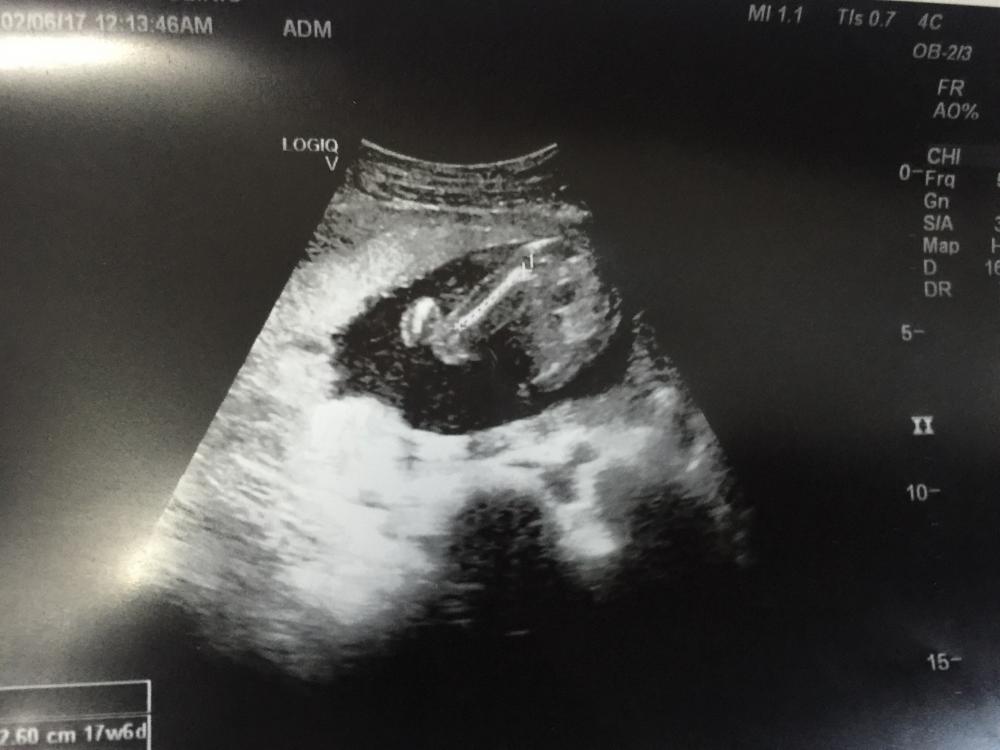

السلام عليكم اللي عندهم خبرة ب السونار